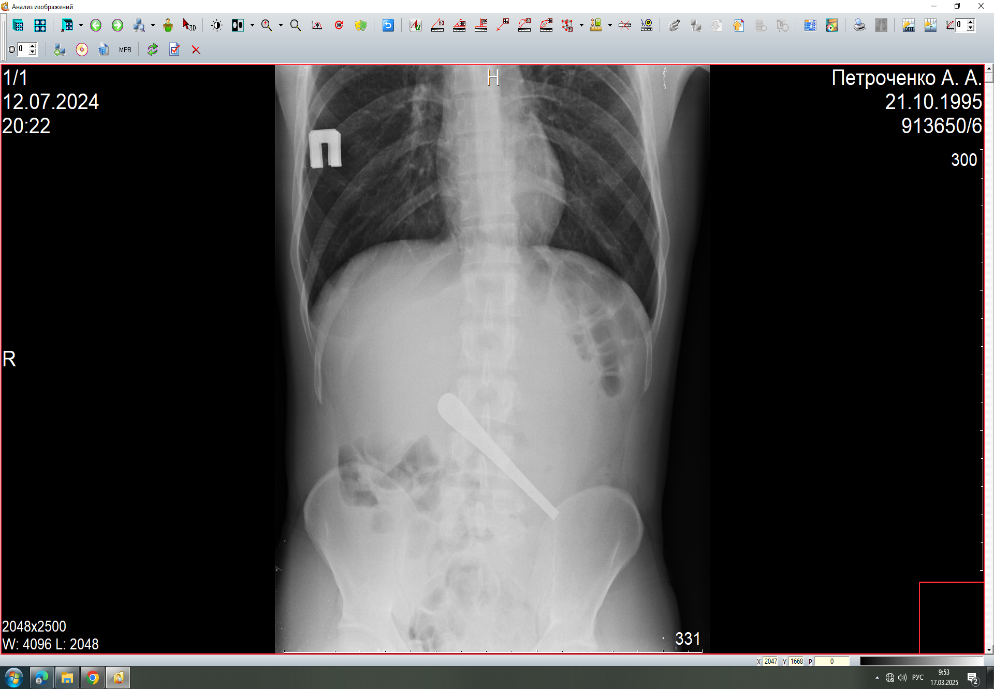

Диагностика рентгенпозитивных инородных тел успешно проводится с помощью традиционной рентгенографии и ультразвукового исследования (УЗИ) .

Рентген -диагностика.

Выявляется:

- дополнительная тень в зоне интереса;

Особая категория инородных тел в организме человекам – это инородные тела, оставленные в результате хирургических вмешательств. Это относительно редкое осложнение. До 50% всех инородных тел составляют забытые хирургические тампоны, марлевые салфетки дренажные трубки, фрагменты катетеров, хирургические инструменты. Чаще всего инородные тела остаются после полостных операций, реже – после лапароскопических, эндоскопических, чрескожных. Наиболее распространенными локализациями ИТ являются брюшная полость, полость таза, также описаны случаи их нахождения в грудной, плевральной, перикардиальной полостях, забрюшинном пространстве, полости черепа, мягких тканях.

- целесообразно использование хирургического материала рентгеноконтрастными метками, что облегчает их обнаружение при лучевой диагностике.